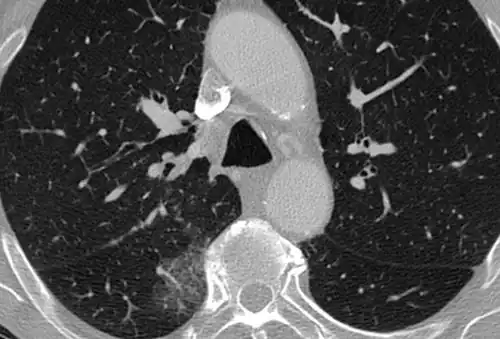

High-resolution CT image showing ground-glass opacities in the periphery of both lungs in a patient with COVID-19 (red arrows). The adjacent normal lung tissue with lower attenuation appears as darker areas.

CT image in patient with COVID-19 showing bilateral ground-glass opacities at the periphery of both lungs.

Ground-glass opacity is among the most common imaging findings in patients with confirmed COVID-19.[16][17] One systematic review found that among patients with COVID-19 and abnormal lung findings on CT, greater than 80% had GGOs, with greater than 50% having mixed GGOs and consolidation.[16] GGOs with mixed consolidation has most often been found in elderly populations.[18] Several studies have described a pattern among initial, intermediate, and hospital discharge imaging findings in the disease course of COVID-19. Most commonly, initial CT imaging reveals bilateral GGOs at the periphery of the lungs. During initial stages, this is most often found in the lower lobes, although involvement of the upper lobes and right middle lobe has also been reported early in the disease course.[16][18] This is in contrast to the two similar coronaviruses, SARS and MERS, which more commonly involve only one lung on initial imaging.[19][20] As the COVID-19 infection progresses, GGOs typically become more diffuse and often progress to consolidation.[11][18] This is sometimes accompanied by the development of a crazy paving pattern and interlobular septal thickening.[18] In many cases the most severe pulmonary CT abnormalities occurred within 2 weeks after symptoms began.[17] At this point, many individuals begin showing resolution of consolidation and GGOs as symptoms improve. However, some patients have worsening symptoms and imaging findings, with further increase in septal thickening, GGOs, and consolidation. These patients may develop lung "white-out" with progression to acute respiratory distress syndrome (ARDS) requiring treatment escalation.[17][21]

Preliminary reports have shown many patients have residual GGOs at time of discharge from the hospital. Due to the novelty of COVID-19, large studies investigating the long-term pulmonary CT changes have yet to be completed. However, long-term pulmonary changes have been seen in patients after recovery from SARS and MERS, suggesting the possibility of similar long-term complications in patients who have recovered from acute COVID-19 infection.[22]